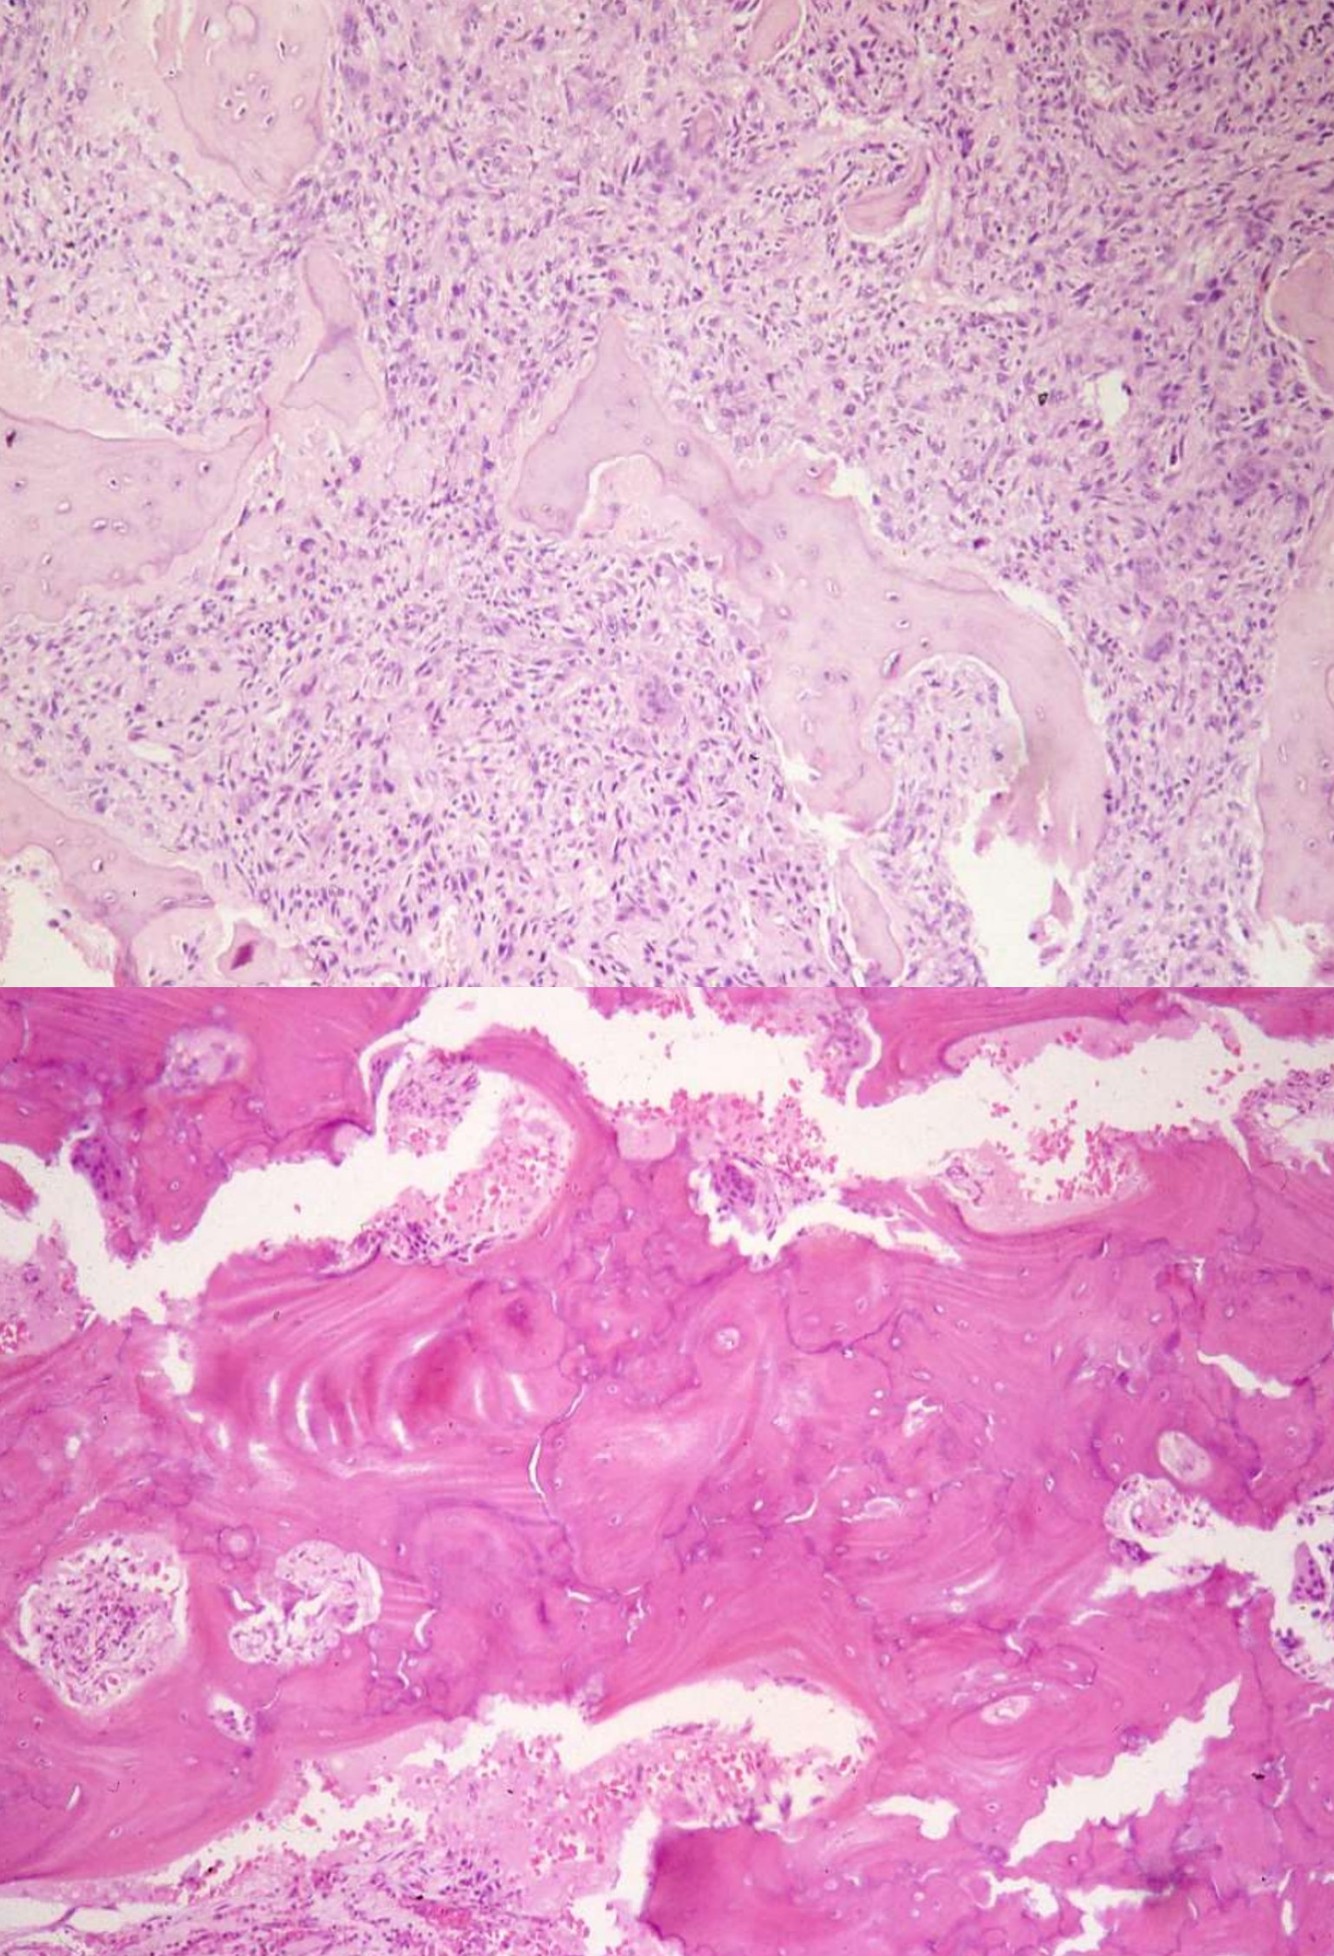

SURFACE OSTEOSARCOMA

PAROSTEAL OSTEOSARCOMA

PERIOSTEAL OSTEOSARCOMA

HIGH-GRADE SURFACE OSTEOSARCOMA

FIBROUS DYSPLASIA